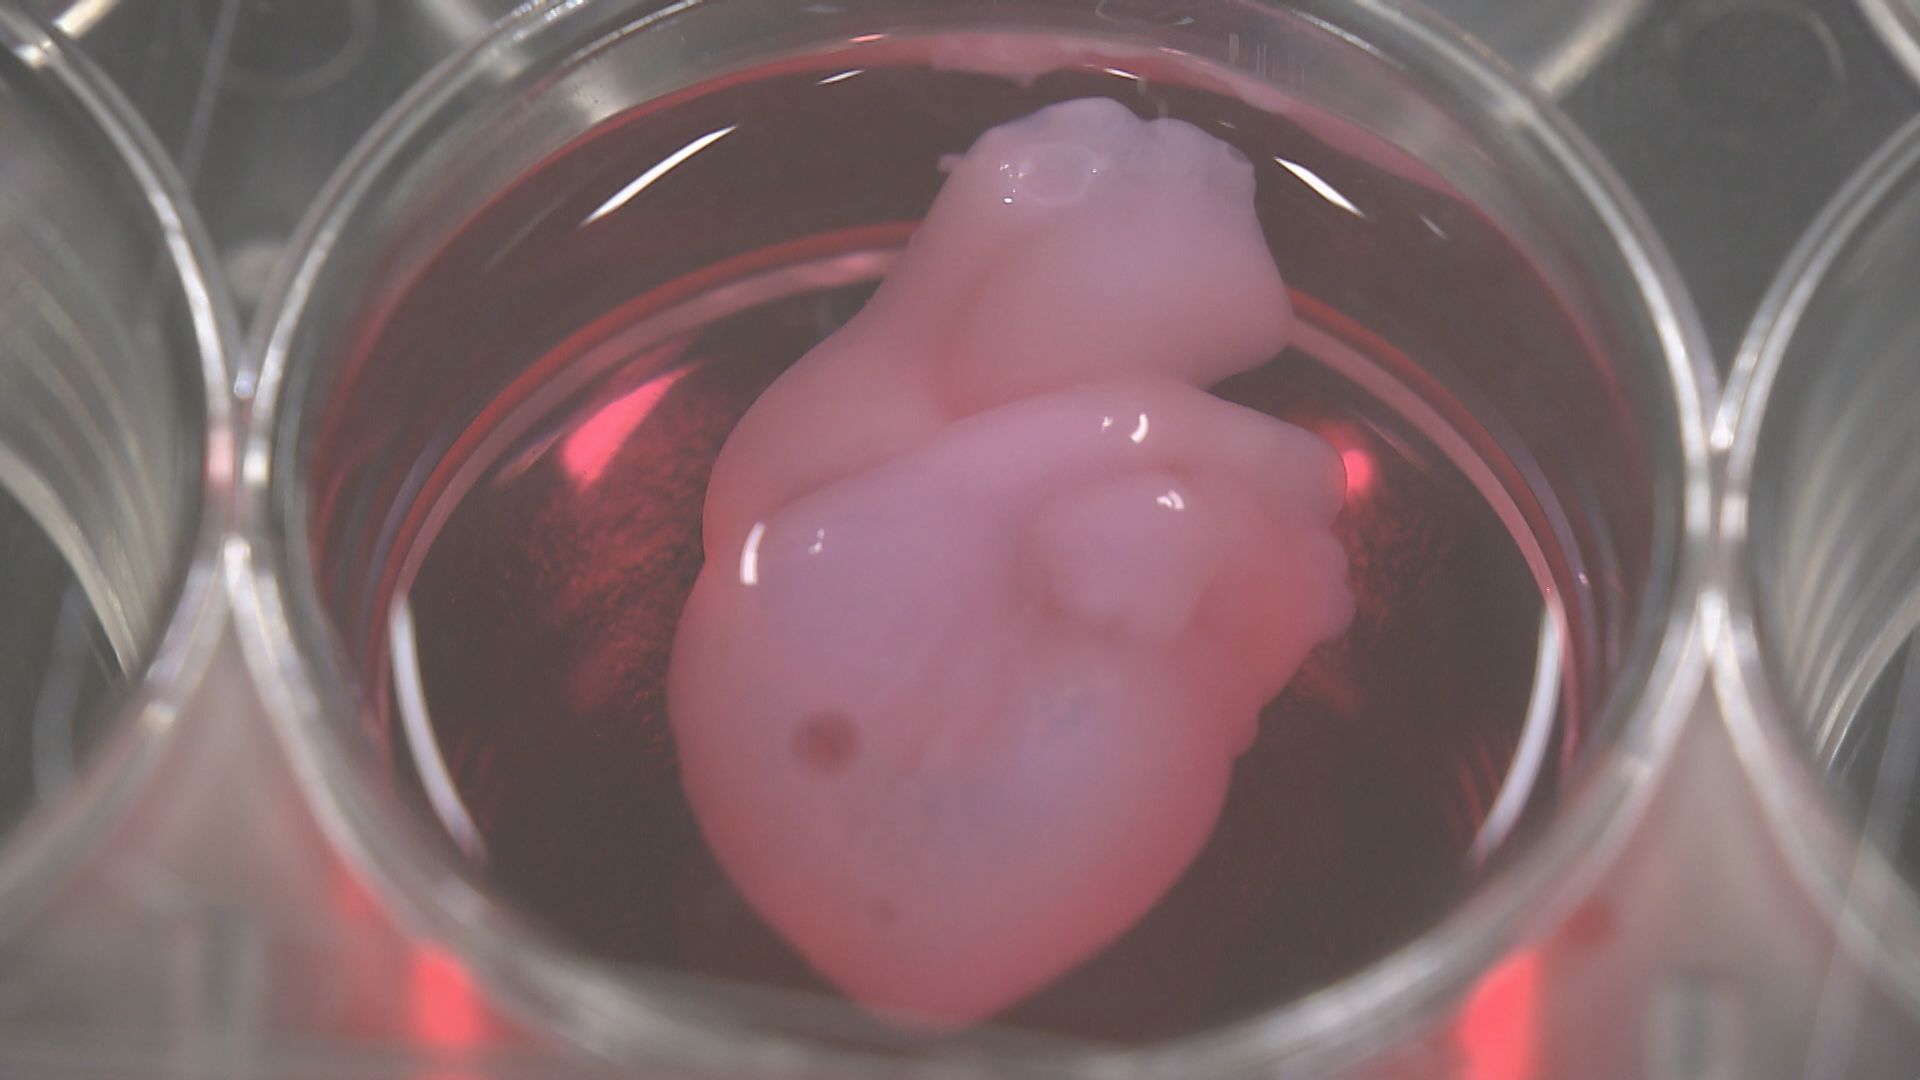

「ドク、ドク、ドク」

赤い液体の中で拍動する、親指ほどの心臓。

訪れた人がスマホ片手に展示を取り囲む。

「ほんまに動いてる。すげぇ」

「未来や、これは未来やね」

そんな声が聞こえてくる。

■万博の目玉「iPS心臓」に挑んだ医師と科学者

大阪・関西万博の目玉の一つ「iPS心臓」モデル。

展示されているパソナパビリオンには、開幕からおよそ3カ月で100万人以上が訪れた。

この心筋シートの技術を応用し、作成されたのが万博の「iPS心臓モデル」だ。

■開幕直前まで続いた微調整 完成した「iPS心臓モデル」

ちょうどいい硬さで、実際の心臓のように動くモデルを目指した結果、最終的にたどり着いたのが、厚さ0.1ミリ、3.5センチの大きさだった。

心筋細胞そのものは、1カ月以上生き続けるものの、「iPS心臓モデル」は製造して1週間後に目視でわかる拍動をはじめ、その後2週間ほどで拍動が鈍くなる。

万博の開催期間中は、目視で拍動がわかるiPS心臓モデルの展示を継続するために、展示用に2つ、予備1つの合計3つの心臓モデルを常に切らなさないようパビリオンに置いている。

作成されたiPS心臓の内部は空洞で、弁や心室はないため、実際の心臓と同じく血液を循環させることはできない。

けれども、iPS細胞から作られた心筋細胞およそ1~2億個が、培養液の温度が人の体温に到達すると自発的に動き、実際の心臓のようにドクドクと拍動する。